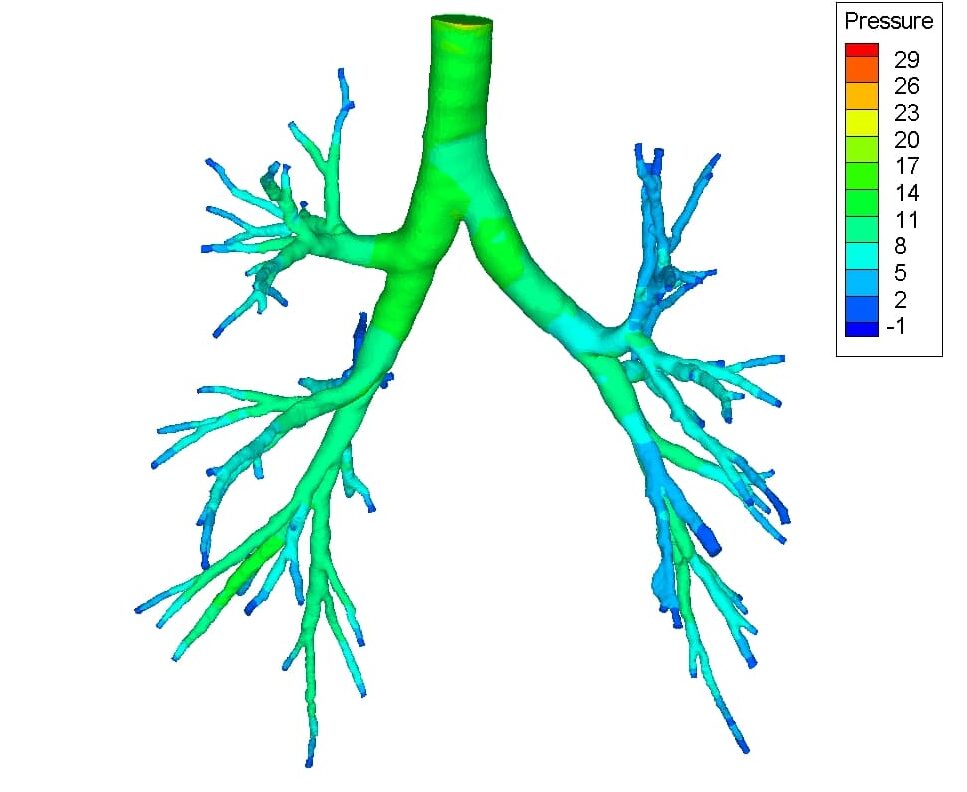

CFD is a branch of fluid mechanics that utilizes different computational techniques to analyze fluid flow behavior and patterns. Biomedical Engineering CFDS abbreviation meaning defined here. Abstract The biomedical research with the aid of CFD software is still emerging which incorporated the physiology and pathophysiology of cardiovascular system and respiratory system through.

Search for PhD funding scholarships studentships in the UK Europe and around the world. CFD is capable of providing valuable hemodynamics which is useful in the clinical assessment of heart performance and the early diagnosis of heart dysfunction 3 6 7. The review then focuses on the applications of CFD in biomedical problems including cardiovascular diseases airflow pattern and aerosol deposition in lungs cerebrospinal fluid flow in brain and for artificial organ design analysis.